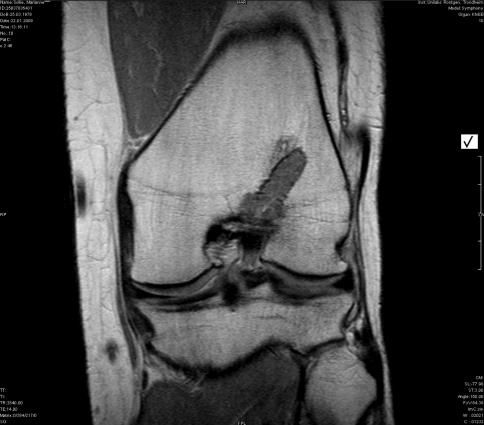

The clinical and functional results were satisfactory in both groups. There were no significant differences between the groups in any parameter measured, except for better Pivot shift results in the bioscrew group (P = 0.04). The MRI evaluation showed degradation of the bioscrews. A residual screw tract which appeared threaded was seen in the tibia in 11 of the 16 patients. There was no sign of bony ingrowth in the previous screw site in the tibia in any of the patients.

两组的临床和功能结果均令人满意。除了生物螺钉组的 Pivot shift 结果更好(P=0.04)外,两组之间在测量的任何参数上均无显著差异。MRI 评估显示生物螺钉降解。在 16 名患者中的 11 名患者中,胫骨中的生物螺钉残留的螺钉通道呈螺纹状。在任何患者中,胫骨中先前螺钉部位均无骨内生长的迹象。